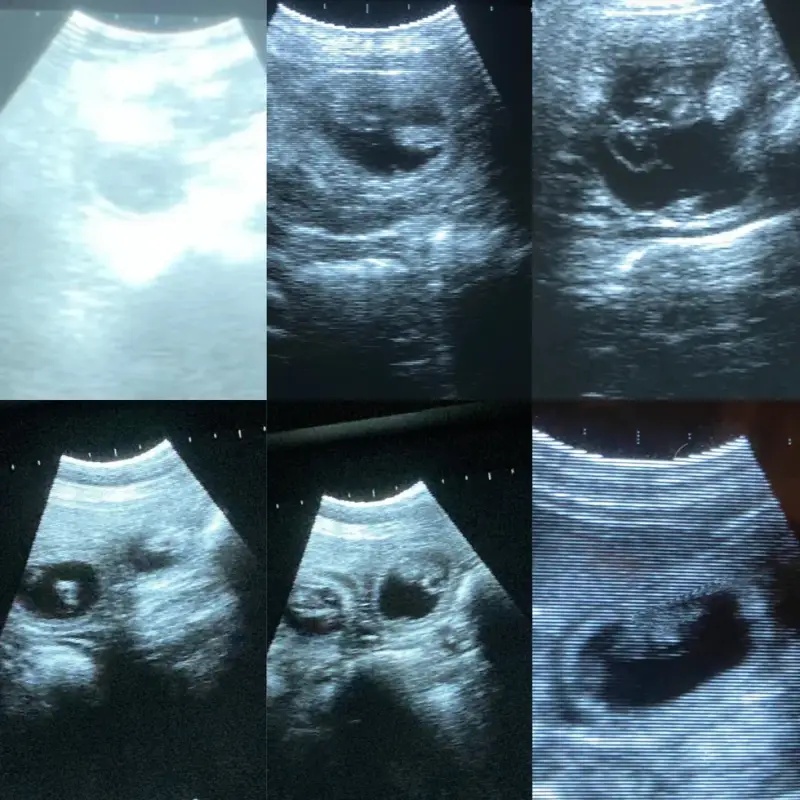

Dracht echo

vanaf heden ook mogelijk om hier met 28 dagen een echo te laten maken. Ik reken enkel kosten als de teef ook drachtig is.

kosten €35

Op locatie ook mogelijk maar dan rekenen we €0,21 per kilometer (deze kosten worden ook gerekend als ze niet drachtig is)